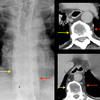

CT nl peric 1

CT Nl Peric 2